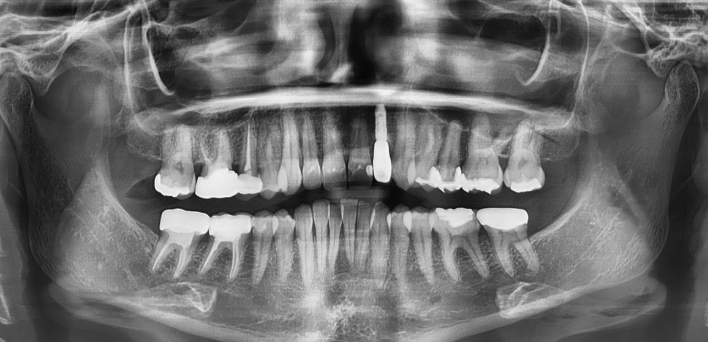

임플란트 : 손 ** 님 (50대)

Before Before

2020.02.30

환자 특징

환자 특징01무치악 상태

환자 특징02수년간 무치악으로 지내심

임플란트가 불가능할것이라

생각하고 내원

위, 아래 6개씩 식립

디지털 풀아치 임플란트